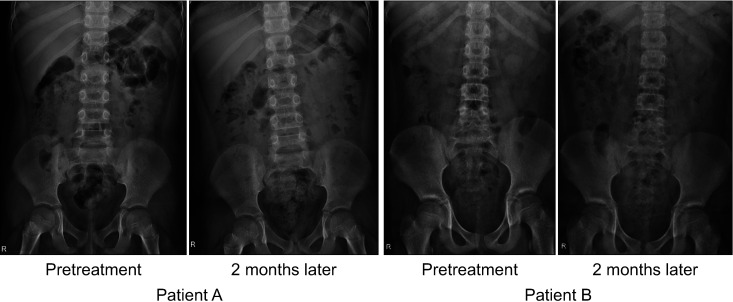

Materials and methods: Forty-five patients with lower urinary tract dysfunction (LUTD) received polyethylene glycol for 2 months before bladder medication for LUTD. Based on partial response to LUTD following treatment, we divided the patients into LUTD-fecal impaction (FI) and LUTD not attributed to FI (LUTD-NFI) groups. Pre/post-treatment kidney, ureter, and bladder (KUB) were compared with respect to several radiographic parameters. Items with significant changes after treatment were included in the scoring system. The accuracy and inter-rater agreement were also evaluated.

Results: Cecal dilation, descending colon dilation, fecal quality, and overall haziness were found to undergo significant changes after laxative treatment. We assigned 0 to 2 points for each item, with a total score of 8. Receiver operating characteristic curve analysis revealed a cutoff value of 5 between LUTD-FI and LUTD-NFI, with 79% sensitivity and 88% specificity. The scoring system was instructed to six doctors who were unaware of it and was then tested on previous patients, which showed a substantial concordance rate (κ=0.79, p<0.05).